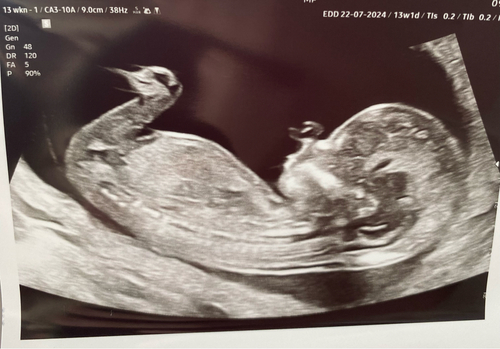

Dit is een echo van 11 weken precies. De verloskundige zij misschien wel een lucky shot wat betreft de nub. @firstblessing @peterpan kunnen jullie hier al iets op zien? Of is het echt nog te vroeg?

Is nog te vroeg maar voor nu is nog meisje maar na 12 weken is het beter en betrouwbaarder om het te weten😊

Nee, te vroeg.